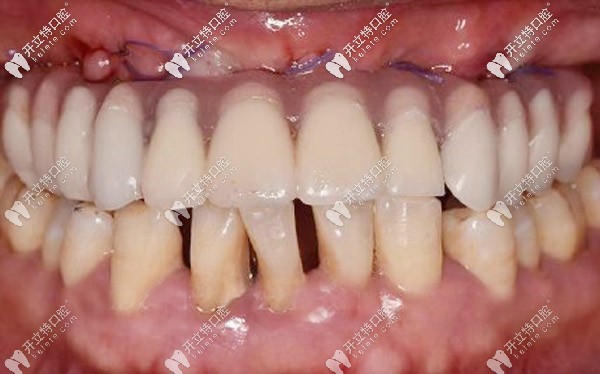

與周老先生進(jìn)行溝通后,確定了種植體嵌入位置、數(shù)量、種植深度、植體傾斜角度等等,并采用上頜6顆即刻種植技術(shù),運(yùn)用“數(shù)字化動(dòng)態(tài)導(dǎo)航種植”方案。

全程監(jiān)控種植位點(diǎn)、角度、深度,能夠避免損傷重要的解剖結(jié)構(gòu)。這樣做可以節(jié)省大量的種植時(shí)間,縮短牙骨暴露在外的時(shí)間,保存了牙骨的活性,有利于植體和牙槽骨的緊密結(jié)合。